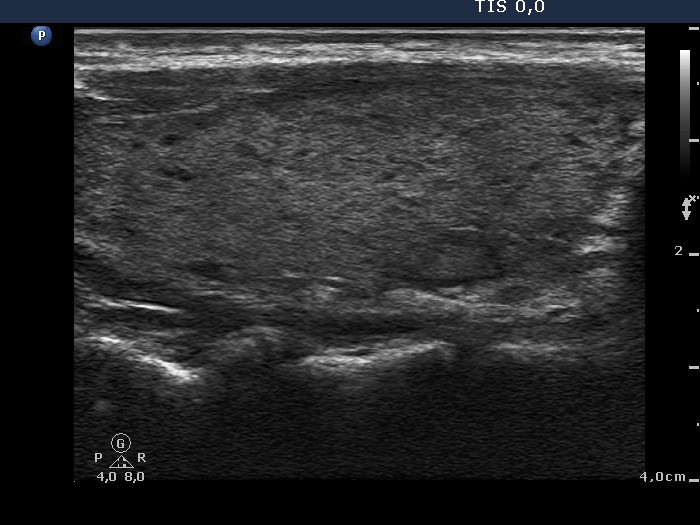

100 consecutive cases of papillary cancer - case 041 (ultrasonographic picture 2)

Right lobe, longitudinal view.